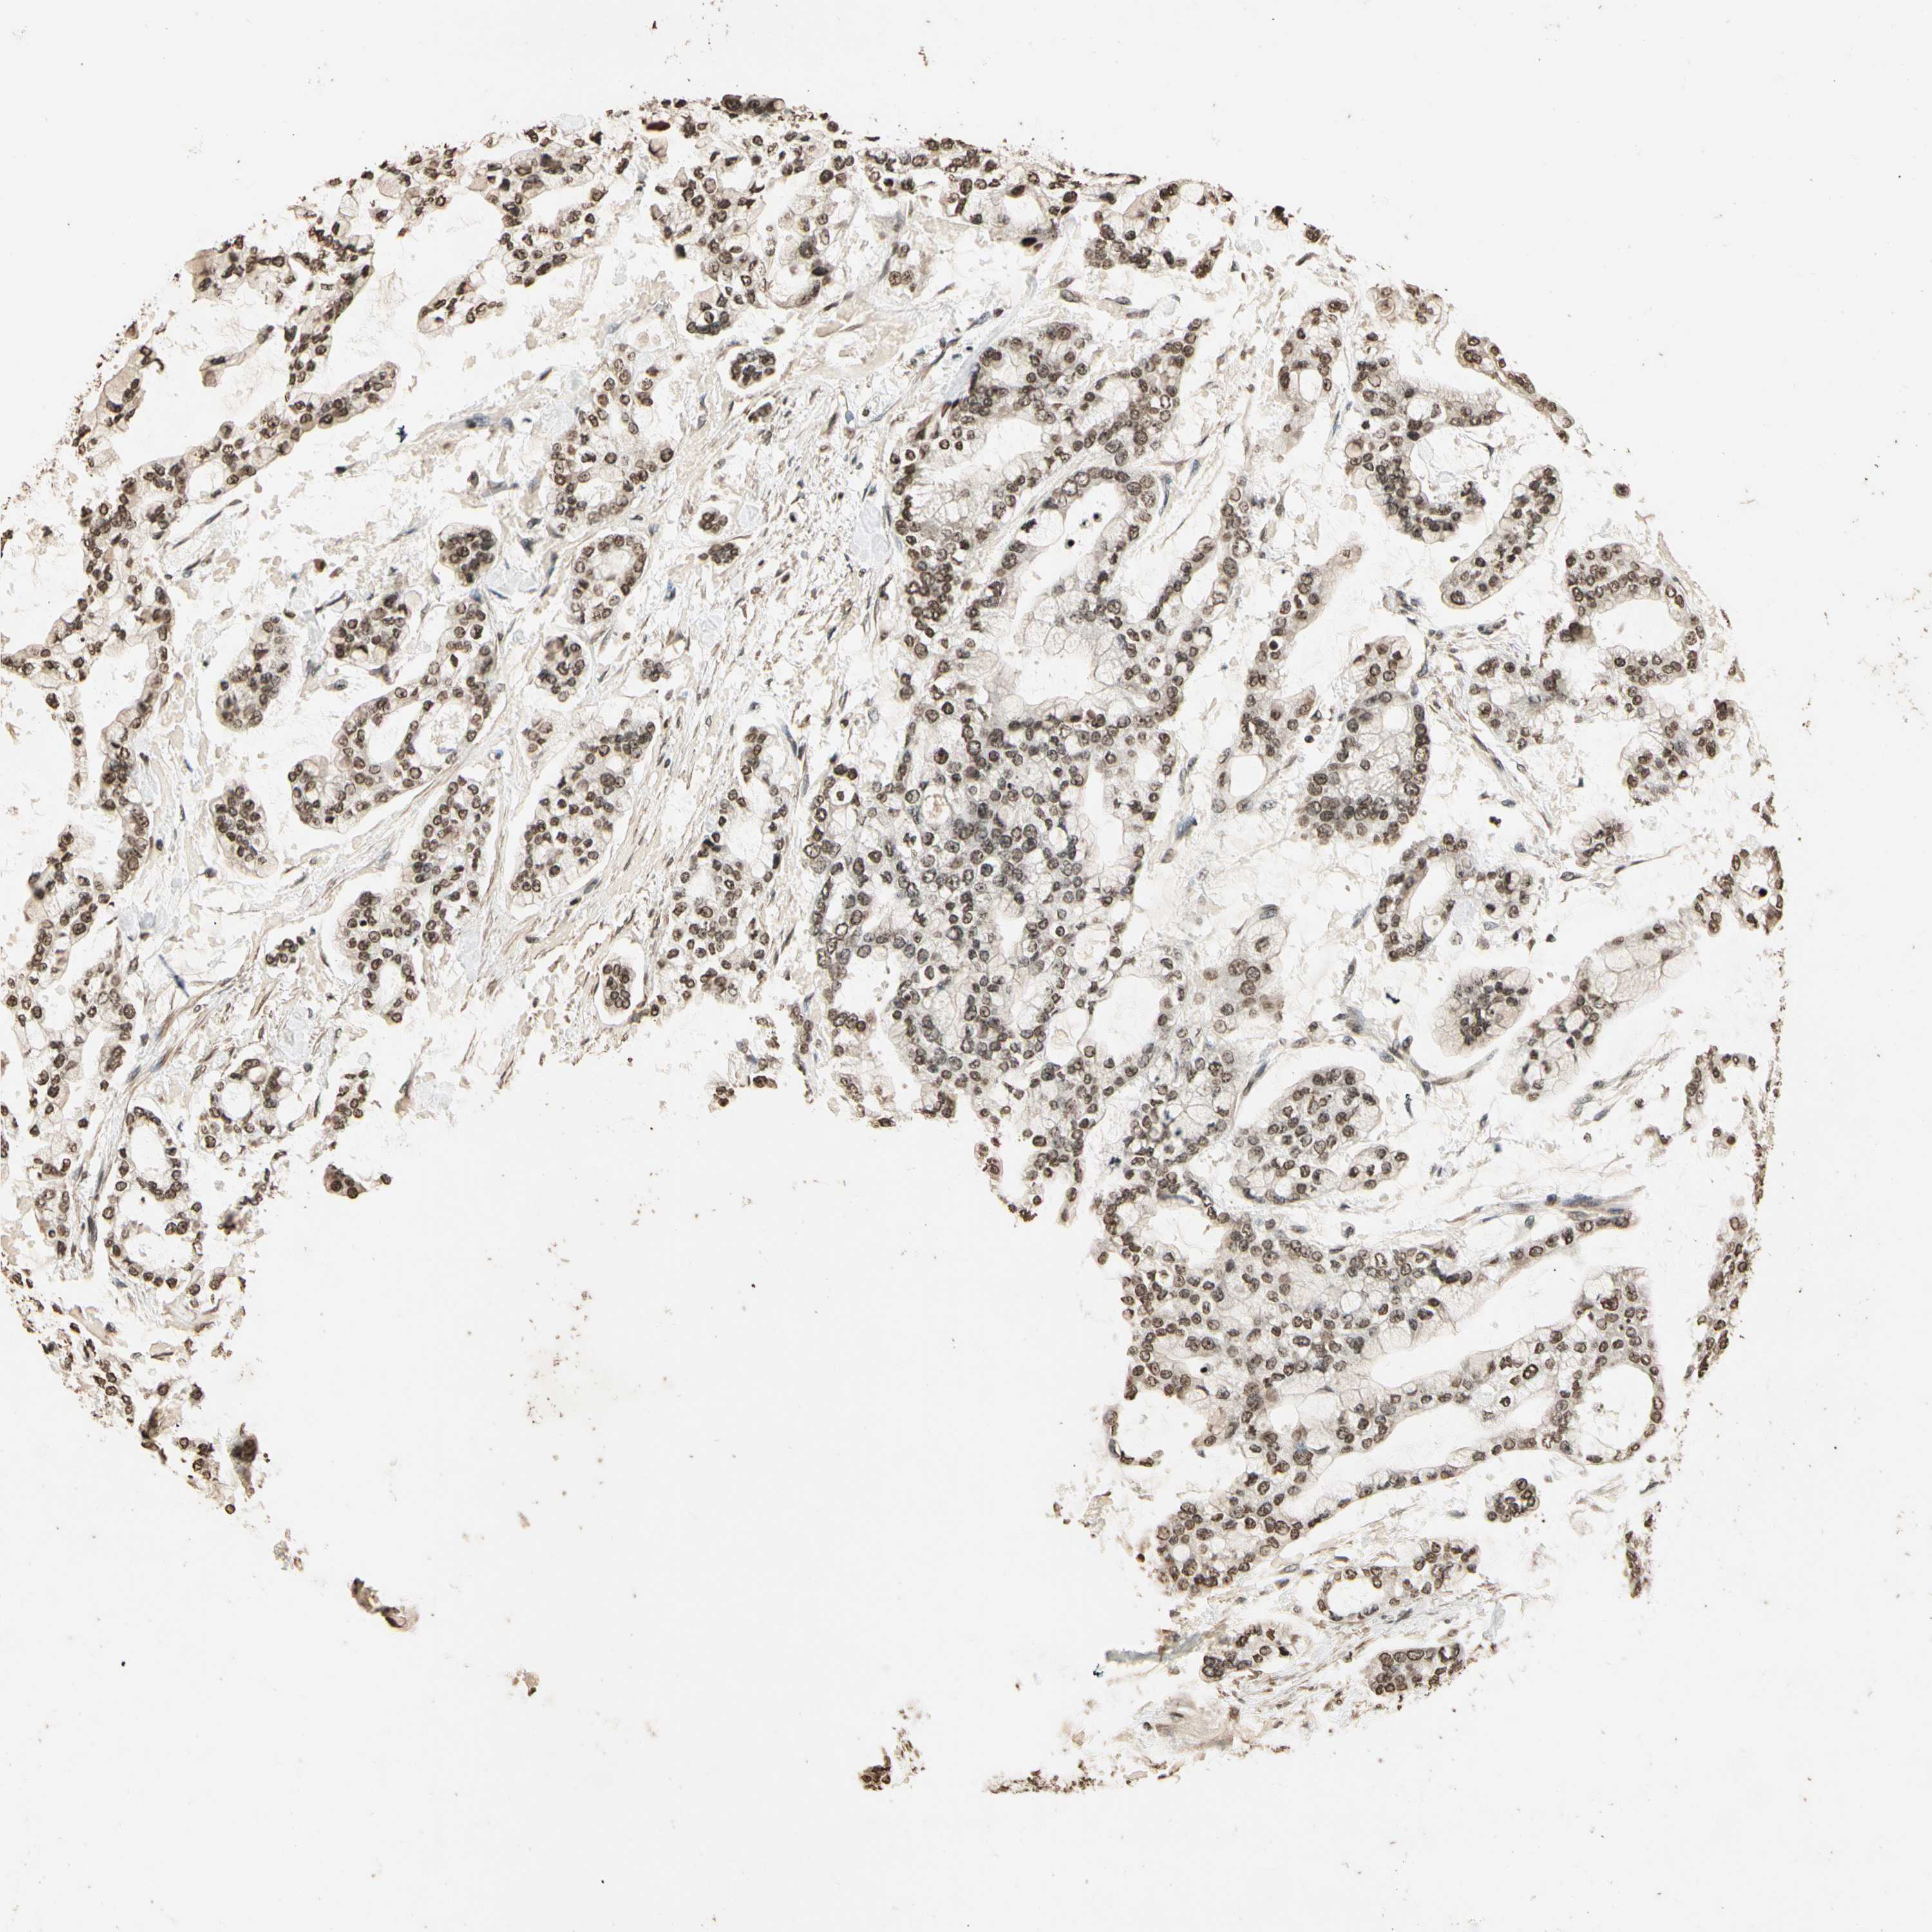

STOMACH CANCER - Protein expressioni

A mouse-over function shows sample information and annotation data. Click on an image to view it in a full screen mode. Samples can be filtered based on level of antibody staining by selecting one or several of the following categories: high, medium, low and not detected. The assay and annotation is described here.

Antibody stainingi

Antibody staining in the annotated cell types in the current human tissue is reported as not detected, low, medium, or high, based on conventional immunohistochemistry profiling in selected tissues. This score is based on the combination of the staining intensity and fraction of stained cells.

Each image is clickable and will lead to virtual microscopy that enables deeper exploration of all samples and also displays staining intensity scores, fraction scores and subcellular localization as well as patient and tissue information for each sample.

Antibody HPA019039

Antibody CAB009058

Staining

High

Medium

Low

Not detected

Intensity

Strong

Moderate

Weak

Negative

Quantity

>75%

75%-25%

<25%

None

Location

Nuclear

Cytoplasmic/membranous

Cytoplasmic/membranous,nuclear

Adenocarcinoma, NOS